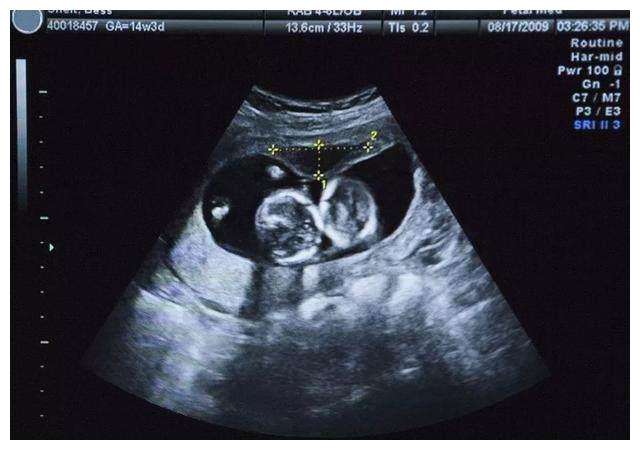

准妈妈怀孕的第一个月称胎芽期,肚子里的小生命,从这个时候开始生长发育,而且他的速度比较快,30—40天形成的是胎囊,40—50天形成的是胎芽,50—60天形成胎心,所以一般的做B超应该是在60天左右的时候做。在孕 8 周以前,都称为胚胎。这时基本上能够看到胎囊、胎芽、胎心是否正常。也是胎宝宝初步形成的一个的重要过程。

一般情况下,在怀孕第八到第十周左右去做B超检查的时候,就能够看到肚子里小家伙的胎心了,所以说在这个时候进行B超或者是彩超的检查时,可以清晰的看到心脏波动的血液信号。胎心胎芽发育良好,就会渐渐的形成胎儿。

所以说在怀孕早期,如果准妈妈在检查的时候没有出现,也不要太过于担心,不要过早的去决定引产,看不到胎心可能会因为自己月经周期不规律,或者是排卵期较晚导致的,受精卵着床较晚,这样的话胎心胎芽出现的时间也,会随之推迟,一般情况下也建议妈妈可以在一周之后再进行复查。最好的检测胎心胎芽时间也是在孕八周到孕十周这个时间段。

需要注意的是,若是在孕60天还未检查出胎心胎芽,准妈妈一定要多跑几个医院做好确认,因为这时没检查出胎心胎芽,不排除是医院仪器或卵泡太小的原因,有过特殊案例,在差不多孕12周的时候,才检查出胎心胎芽的。